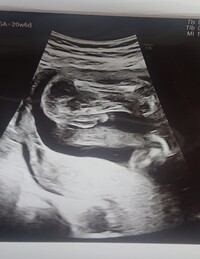

胎児 エコー 男の子 画像

胎児 エコー 男の子 画像-胎児 性別 エコー 写真 男の子 7カ月後半の妊婦健診。 写真の見分け方や男の子、女の子それぞれの見え方の特徴を画像付きで解説します。男の子はピーナツ状の突起物、女の子は木の葉やコーヒー豆が股間に見えますが、ときには判定間違いも起こりApr 30, 17 · 19週で判明!胎児の体勢によるかも 上の子は男の子ですが、はっきり言われたのは7ヶ月の時でした。 それまでなぜか検診の時は横向きとかだったんですよね。 下の子は女の子でしたが、19週で4dで診てもらった時、先生に「女の子だね!」と断言されました。